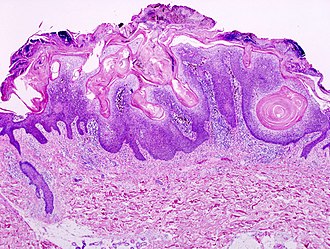

Seborrheic keratosis. H&E stain. | |

Microscopic

Features:[2]

- Raised above skin surface.

- Border sharply demarcated.

- Hyperkeratosis - stratum corneum extra thick.

- May be minimal.

- Usually predominantly basketweave pattern.

- Horn cysts - intraepidermal collections of keratin - key feature.

- Actually invaginations - not true cysts; thus, they may more accurately be called pseudohorn cysts.[4]

- Clusters of cells with brown granular material in the superficial dermis/dermoepidermal junction - pigmented melanocytes.